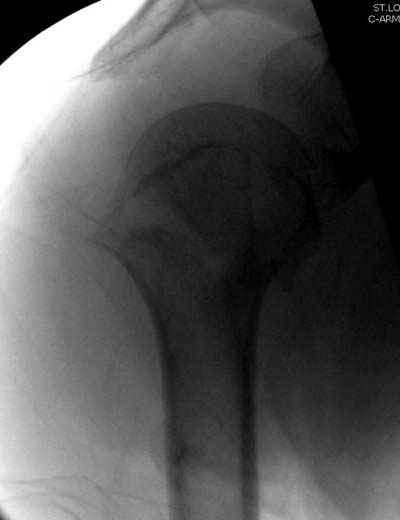

Здесь случай перелома-вывиха плеча, больному 56 лет, после "дважды" закрытой неудачной репозиции, опять же ургентно взяли в операционную, после полного общего обезболивания попытались сделать репозицию, и фиксацию провели спицами.

Больной находился в повязке, примерно напоминяющей косыночную, рекомендованы движения в локтевом суставе и маятниковые движения в плече, спицы удалены в три недели (были случаи миграции)

Больной амбулаторный, предупрежден на случай осложнения АВН головки.